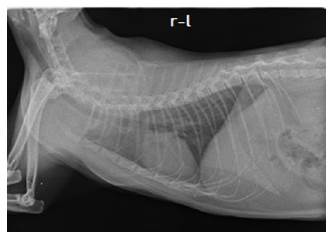

Adicionalmente, se tomaron radiografías ventrodorsal y lateral de tórax con el fin de descartar focos metastásicos. En la misma se apreciaron los campos pulmonares con la radiopacidad esperada, sin evidencia de lesiones focales o difusas, la silueta cardiaca, tráquea y demás estructuras mediastínicas se encontraron con características normales y no se observaron alteraciones óseas (Figura 6).

Las radiografías torácicas para búsqueda de metástasis deben ser repetidas en intervalos determinados debido a que las lesiones neoplásicas metastásicas inferiores a 8 mm pueden pasar inadvertidas.